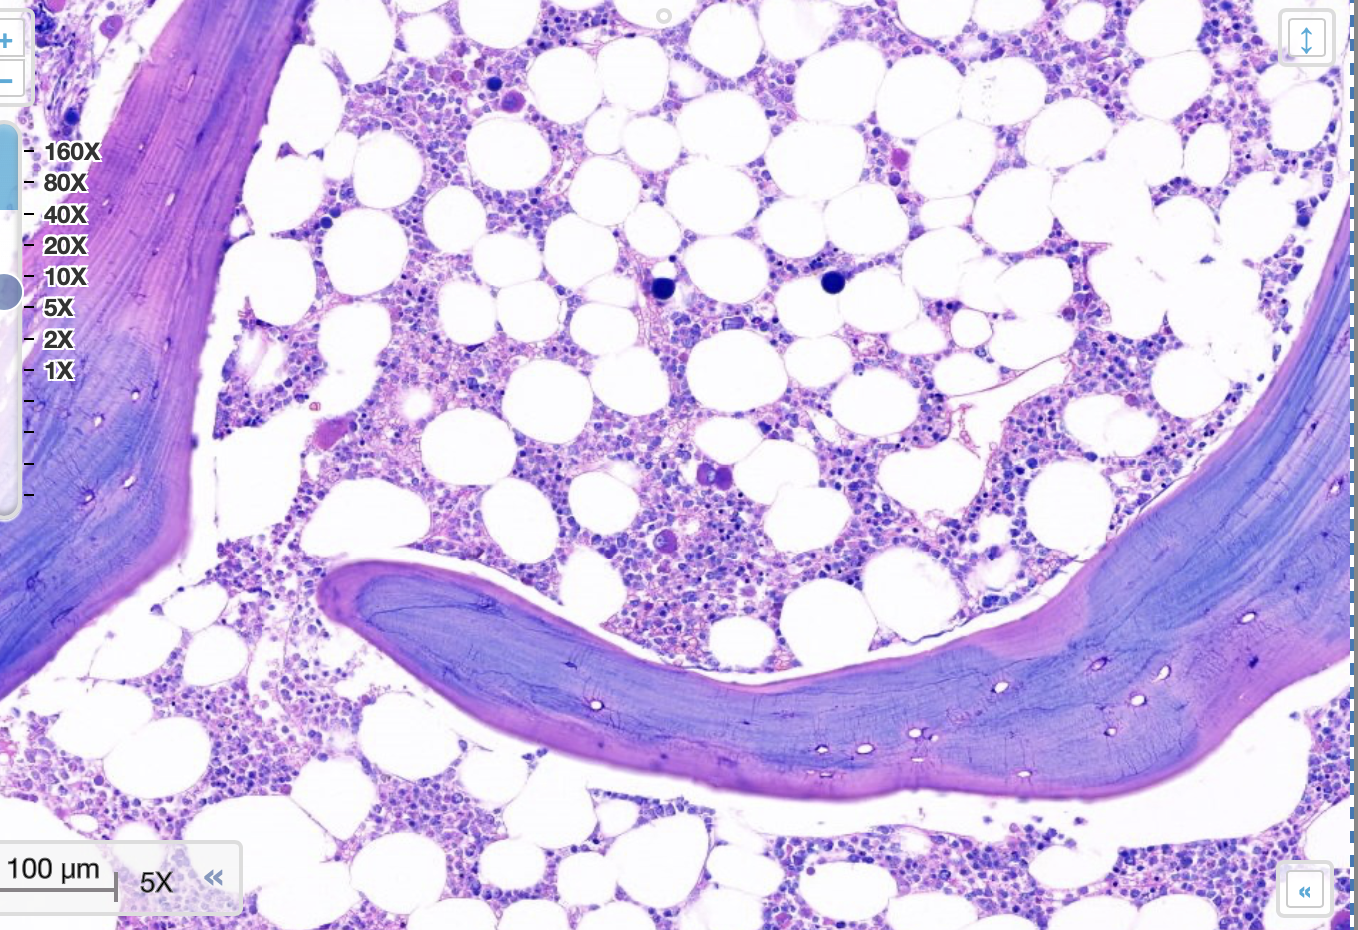

pathologische kenmerken multiple myeloom

mature en abnormale plasmacellen

hypercellulair

anisocytose

nucleoli duidelijk aanwezig

megakaryocyten

voorlopercellen van granulocyten en erythrocyten

vetcellen

osteocytes

multiple myeloom